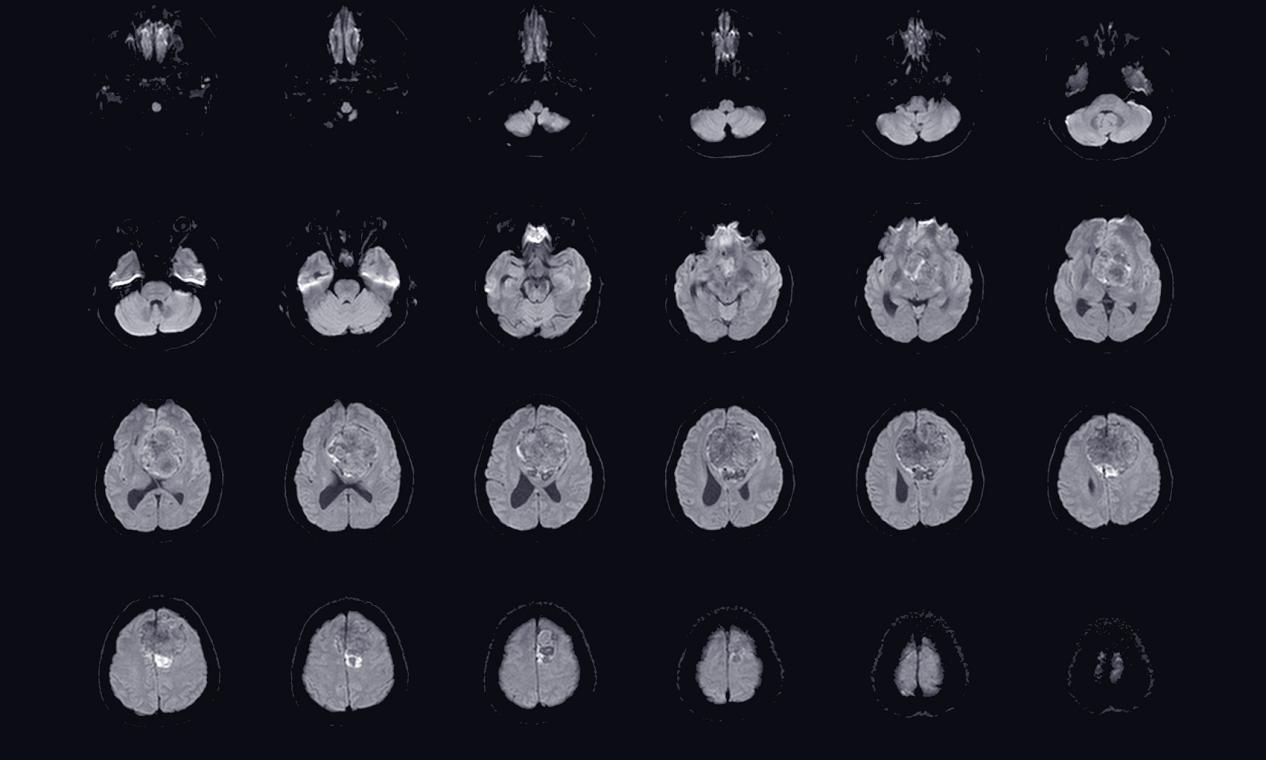

【昆明医科肿瘤医院】脑胶质瘤的晚期存活率

脑胶质瘤是一种恶性肿瘤,随着疾病的进展,患者的晚期存活率可能会降低。然而,许多因素会影响晚期存活率,如年龄、肿瘤类型、治疗方法、肿瘤大小和位置等。根据研究,晚期脑胶质瘤的五年生存率通常低于20%。在一项针对晚期胶质瘤患者的研究中,研究人员发现,在接受标准治疗(...